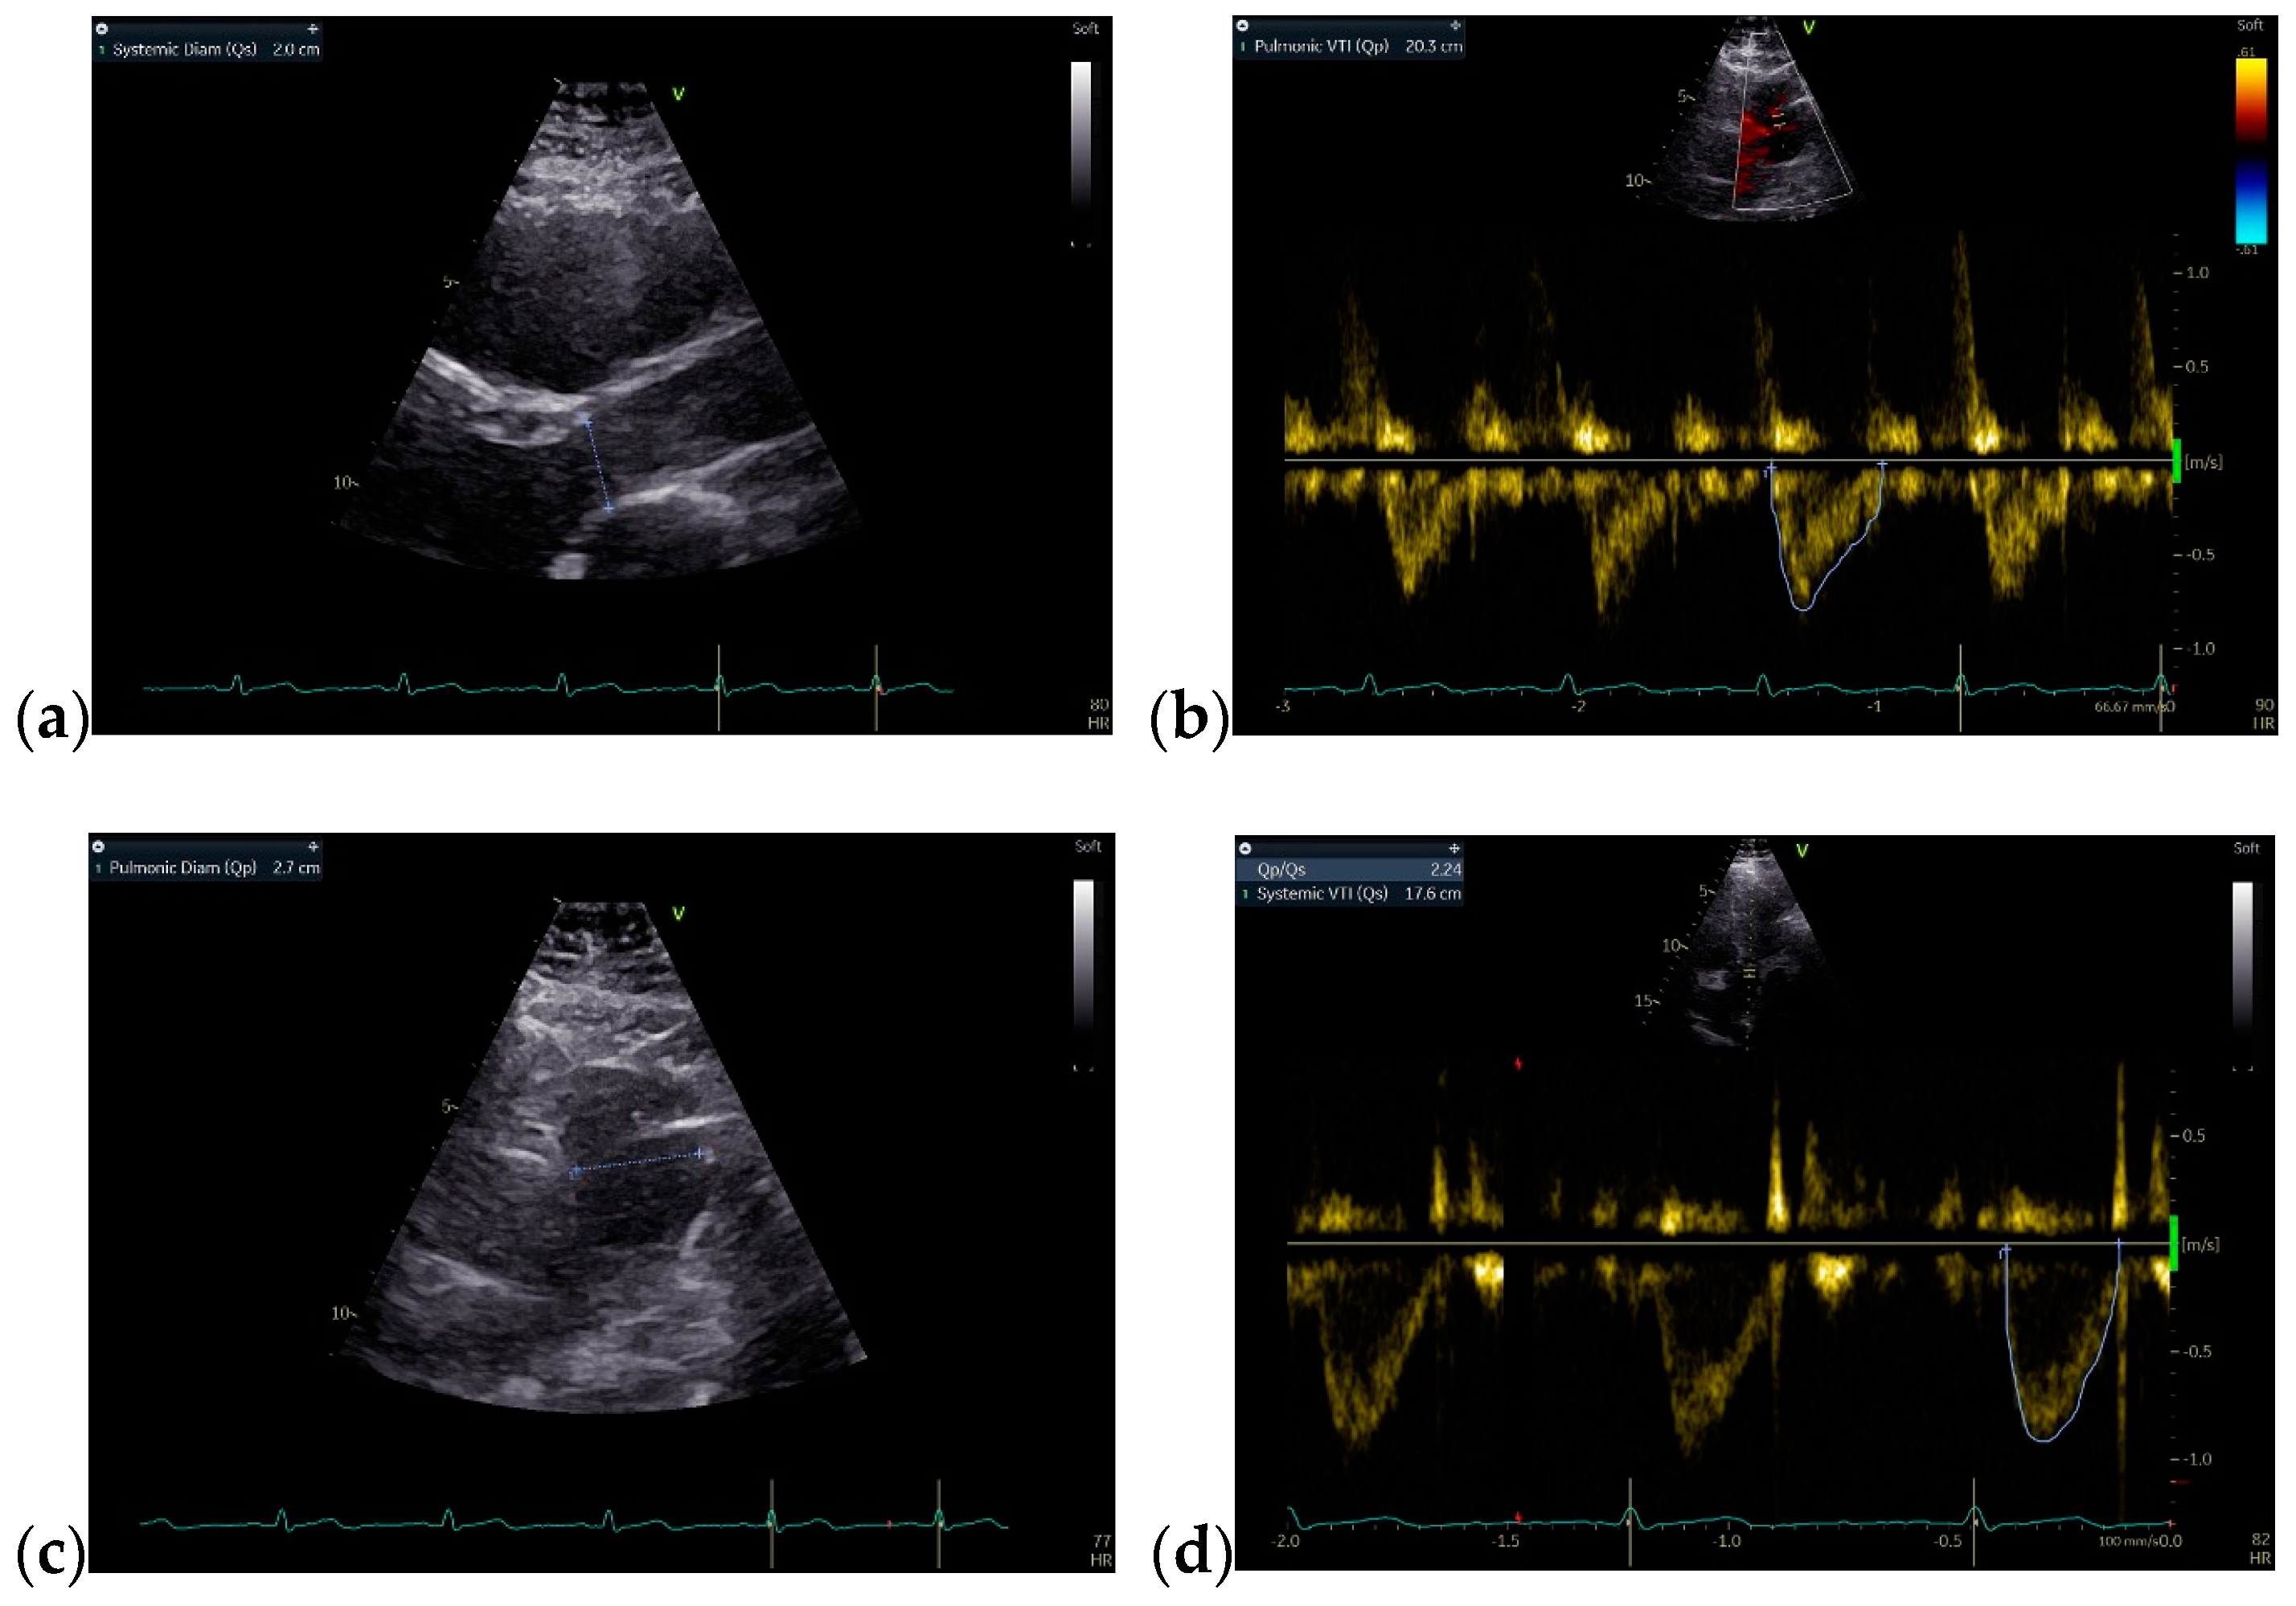

The follow-up TTE evaluation demonstrated a nondilated left ventricle with preserved ejection fraction, dilated right chambers, an increased total volume of RV measuring 339 mL and atrialized RV with a volume of 135 mL, severe functional tricuspid regurgitation, insertion of the septal cusp of the tricuspid valve approximately 2.9 cm from the plane of the tricuspid annulus and ventricular pacing electrode (Figure 12).

Figure 12.

The TTE follow-up evaluation: (a) Apical 4-chamber view: dilated right cavities with a total volume of RV measuring 339 mL; (b) Apical 4-chamber view: atrialized RV volume of 135 mL; (c) Apical 4-chamber view: color Doppler flow revealing severe tricuspid regurgitation; (d) Tricuspid continuous wave Doppler flow: maximum RV-RA gradient = 33.45 mmHg; (e) Apical 4-chamber view: insertion of the septal cusp of the tricuspid valve at approximately 2.9 cm from the plane of the tricuspid annulus; (f) Apical 4-chamber view: end-diastolic left ventricular volume—110 mL. Abbreviations: TTE—transthoracic echocardiography; RV—right ventricle, RA—right atrium.